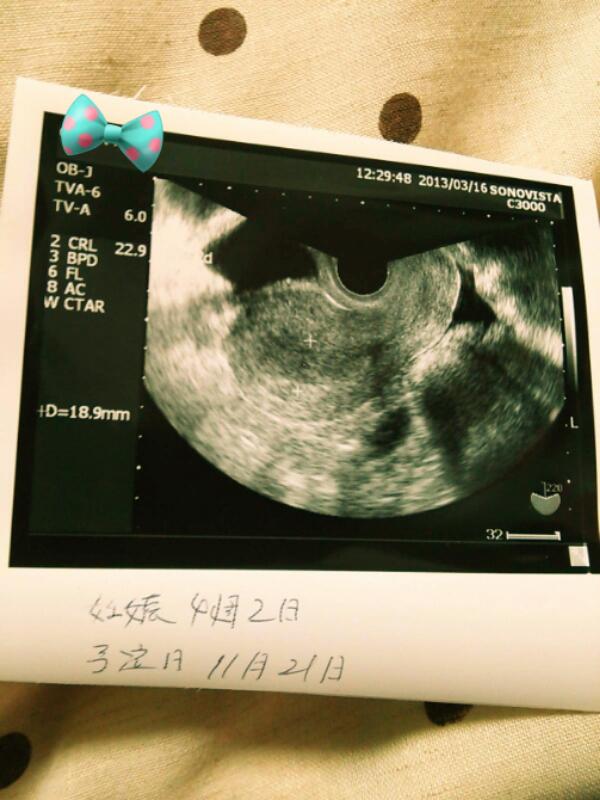

とりあえず、3/16の時のエコー写真。何も見えてない。

てか、胎嚢確認すらできてないのに、出産予定日が書き込まれている…w

上手くいけば、2013年11月21日が予定日なのですね。